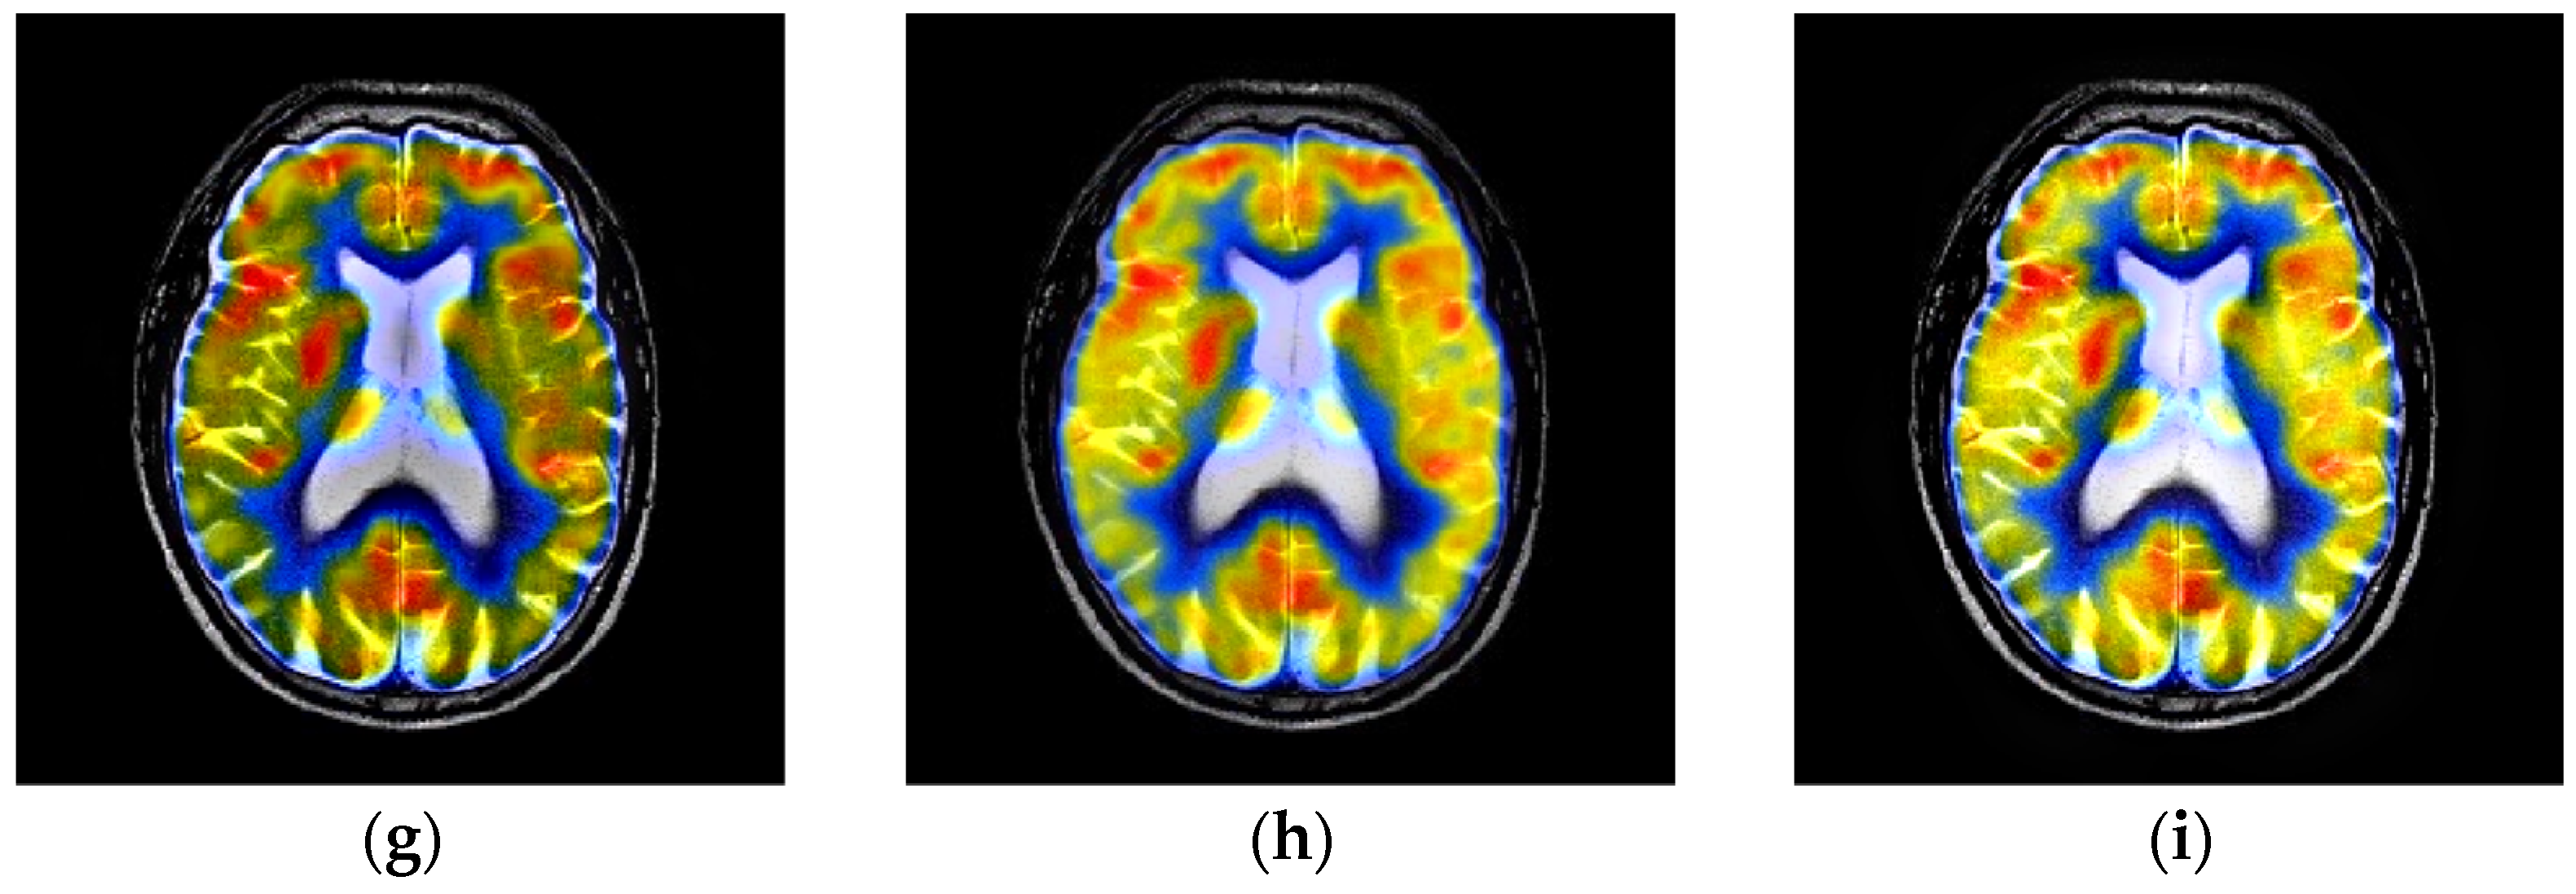

4.2. Comparison of Gray Image Fusion

4.3. Comparison of Anatomical and Functional Image Fusion